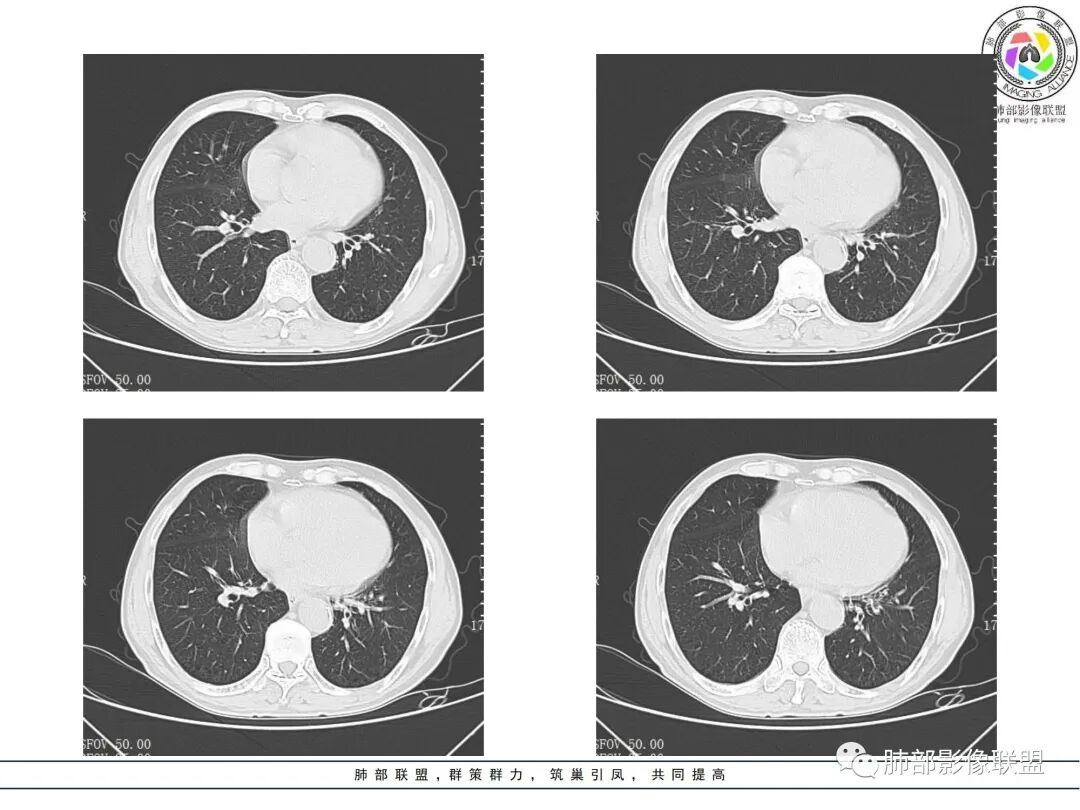

晨读病例,老年男性,乏力,纳差,近来发热,右肺上叶团片状阴影,内见空洞,空洞内壁不光滑,见短液平,增强病灶壁可见不均匀强化,似有边界不清晰的坏死,病灶周围可见片状模糊阴影,考虑恶性病变,鳞癌或腺癌伴感染。

老年男性,肺气肿背景,右肺较大分叶状肿块,密度不均,内坏死空洞形成,坏死区边界不规则,周围多发斑片蜂窝状、网格状高密度影,考虑鳞癌合并感染

右肺上叶及中叶不规则肿块伴周围模糊影,其内小叶间质结节样改变,肿块不均匀强化,坏死及空洞,坏死边界不清,血管显示尚可,考虑腺癌,鉴别淋巴瘤

老年男性,有咳嗽发热。右肺中上叶团状软组织肿块,周围磨玻璃渗出改变,病灶内密度不均,可见低密度坏死及空洞影,空洞内壁凹凸不平,近肺门侧可见明显大面积坏死。近端支气管堵塞不明显。考虑恶性肿瘤伴感染,腺癌?鉴别鳞癌,感染性病变。

右肺上叶团片状阴影,内见空洞,空洞内壁不光滑,偏心,,增强不均匀强化,内有边界不清晰的坏死,病灶周围可见片状模糊阴影,右下肺也有磨玻璃病灶,Crp高,腺癌

70岁男性,发烧病史,右肺巨大肿块,边缘分叶,内部空洞,洞内见附壁结节,局部支气管阻塞,肿块周围见大片阻塞性炎症;实验室检查,炎性指标增高;考虑恶性肿瘤伴阻塞性肺炎,鳞癌可能。

老年男性,乏力,纳差,发热。右肺上叶团片状阴影,密度不均,可见低密度坏死,坏死边界不清,可见空洞形成,见短液平;增强病灶呈不均匀强化,其内血管边缘模糊毛糙;病灶周围可见斑片状渗出病灶,支气管未见明确阻塞。综上考虑肺癌伴感染,鳞癌可能。

老年男性,纳差和发热,炎症指标明显。右肺磨玻璃影伴有肿块,肿块呈膨胀性生长,内部没有气管影。首先考虑感染,并有肿瘤的表现。考虑鳞癌合并感染

右肺上叶实变,密度不均,内可见小气液平,周磨玻璃影,斜裂稍内凹,右下肺可见斑片影,强化可见血管走行自如,右侧胸腔少量积液,考虑感染性病变,努卡?放线菌?

男,70,反复乏力、纳差20天,发热1天。胸部CT:肺气肿背景,右肺上叶中叶大团片影,实变十磨玻璃渗出。增强实性斑片影内密度不均,可见多发低密度坏死及不规则空洞影,空洞内壁尚光滑,血管边缘模糊。支气管管壁增厚,管腔通畅。右下叶可见小片渗出影。考虑支气管肺炎进展?病原考虑能形成肉芽肿、坏死空洞的微生物,TB?奴卡?鉴别鳞癌。